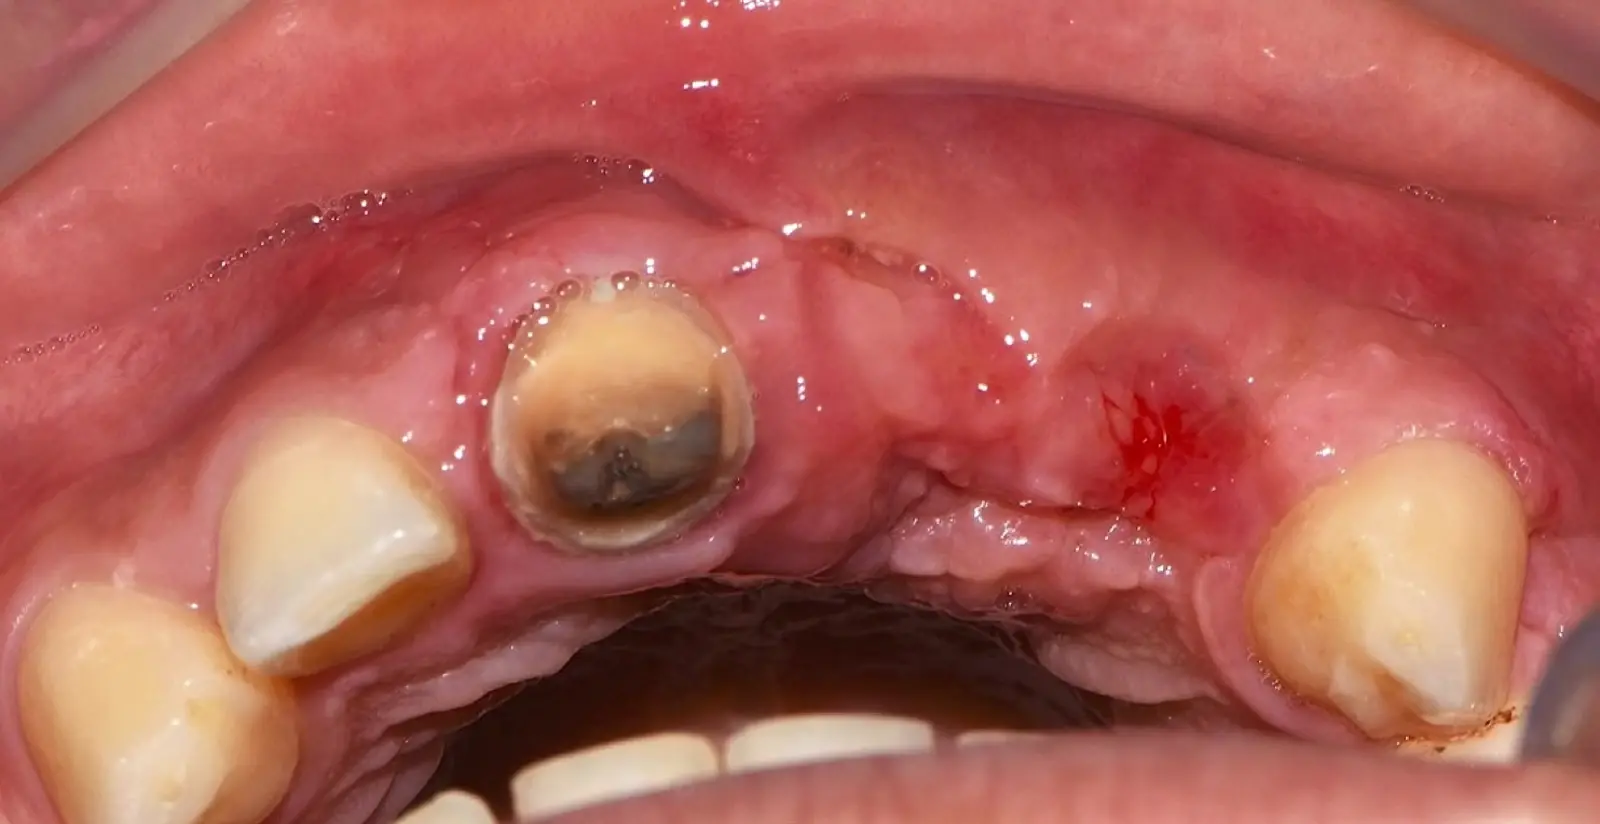

Paciente de sexo femenino de 36 años de edad, llega a la consulta por presentar una restauración protésica inadecuada. En el examen clínico se observa una restauración protésica provisional acrílica sobre las piezas 1.1 y 2.2. Adicionalmente, se aprecia recesión gingival a nivel de la pieza 2.2 y deficiencia horizontal severa de reborde a nivel de la zona edéntula correspondiente a la pieza 2.1. En la evaluación tomográfica se observa ausencia total de tabla ósea vestibular en la pieza 2.2, y se corrobora el déficit en la zona edéntula de la pieza 2.1, para lo cual se indica una reconstrucción de estructuras óseas con hueso en bloque de origen bovino y posteriormente la colocación de implantes dentales.

Figura 34. Vista frontal donde se observa deficiencia vertical del reborde óseo a nivel de las piezas 2.1, 2.2.